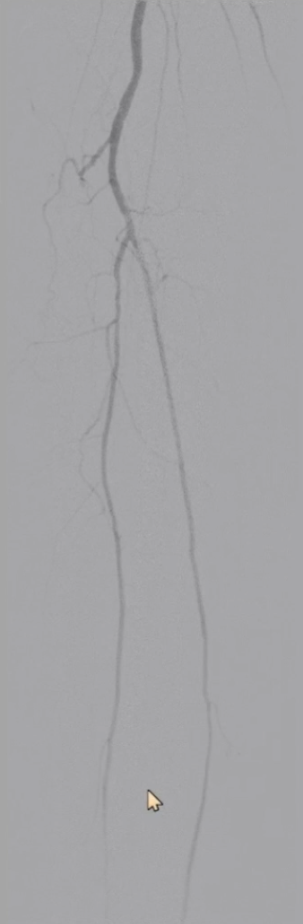

最终造影显示:支架定位准确、形态良好,股浅动脉、腘动脉及膝下动脉显影清晰,血流通畅。